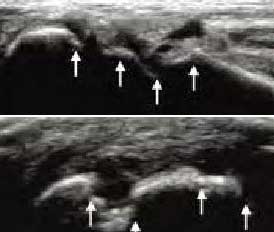

2、清晰显示滑膜异常形态,定量评估RA炎性

类风湿性关节炎以滑膜炎为基本病理改变,超声可观测到关节暗区的范围及厚度,判断有无滑膜增厚、显示不同程度的滑膜均匀或不均匀增厚,分辨滑膜呈绒毛状、团状或结节状结构向关节腔突起的形态。通过对滑膜厚度、水肿、炎性细胞浸润状况的分级、定量评估RA关节内滑膜的炎性程度。

Ⅰ级滑膜增生

轻度滑膜增生,不超过骨面点连线

Ⅱ级滑膜增生

滑膜增生超过骨面点连线,呈绒毛状,但不越过骨干

Ⅲ级滑膜增生

滑膜增生超过骨面点连线,呈团块状延伸超过一侧骨干